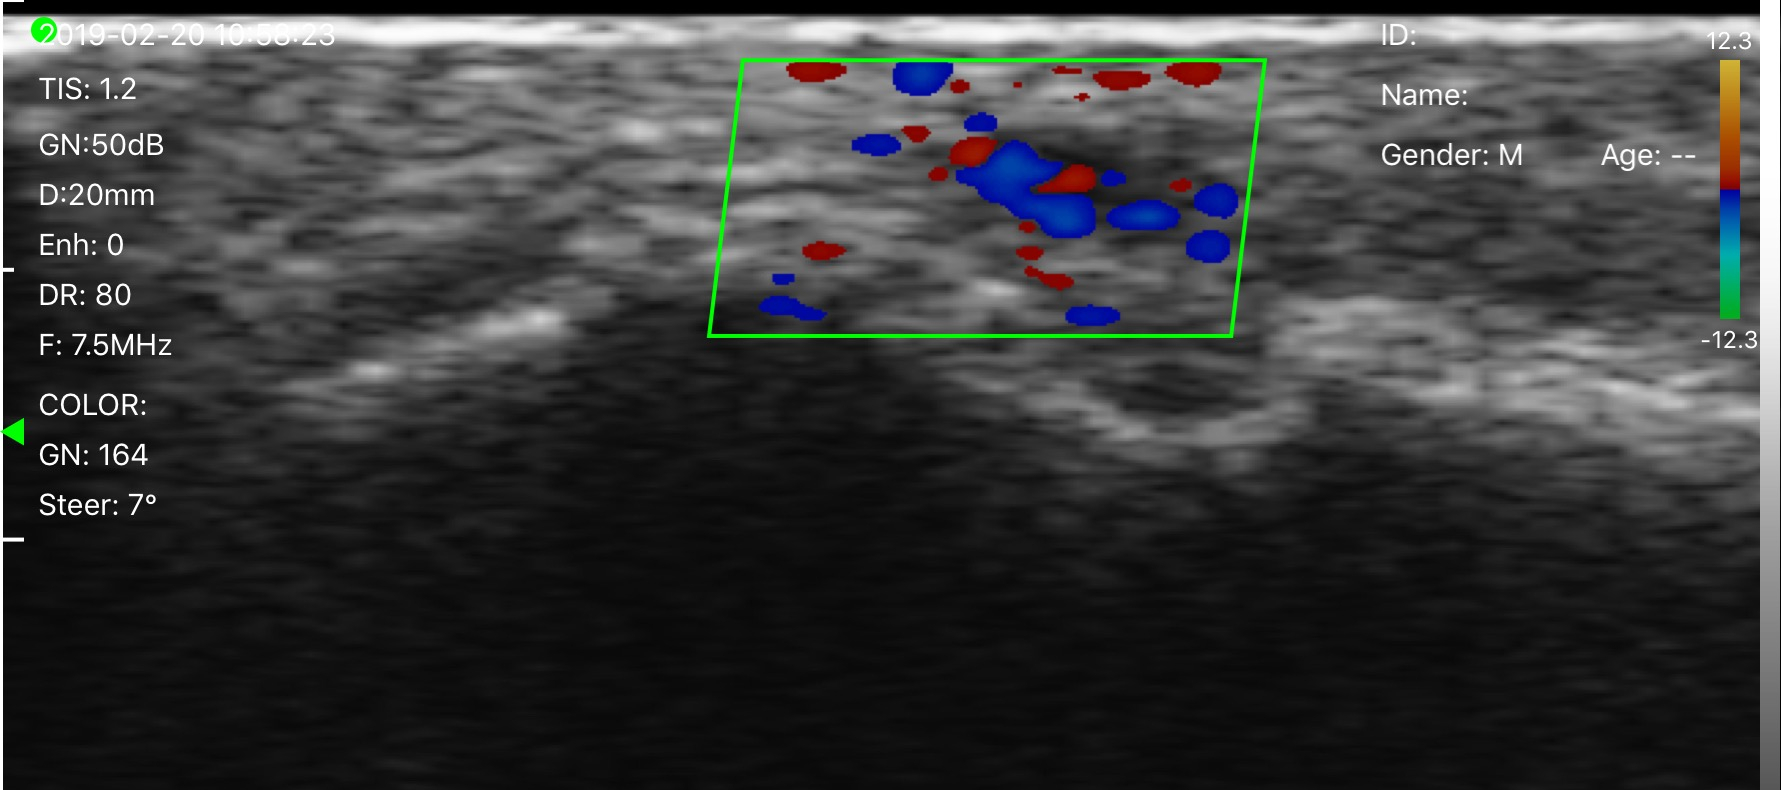

El estudio de ecografía doppler es un estudio no invasivo que permite el diagnóstico de la Trombosis Venosa Profunda con una alta sensibilidad y especificidad.

Es un estudio en el cual se visualiza todo el sistema venoso de las extremidades pudiendo identificar el sitio de obstrucción y la extensión del coágulo. No es doloroso y debe de ser realizado por un médico radiólogo certificado y con alta experiencia.

Vena sana vista a través del ultrasonido